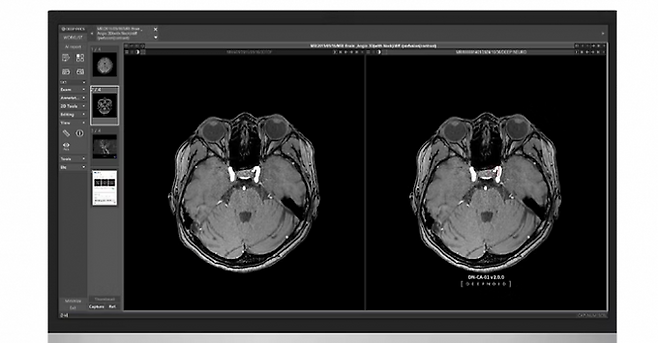

대표적인 솔루션은 MRA 기반 뇌동맥류 진단 솔루션인 ‘딥뉴로(DEEP:NEURO)’와 X-ray 기반 질병 진단 보조 솔루션 ‘딥체스트(DEEP:CHEST)’다. 고 본부장은 "각 솔루션은 의료 영상 데이터를 기반으로 특정 병변을 정밀하게 분석하는 역할을 한다"고 소개했다.

그는 특히 딥뉴로에 대해 “MRA 영상을 기반으로 뇌동맥류를 자동으로 검출하는 국내 최초 국내 솔루션”이라며 “뇌동맥류는 크기가 작을수록 놓치기 쉬운데 딥뉴로는 3mm 이하의 미세한 병변까지 검출할 수 있도록 설계됐다”고 말했다. 통상 임상현장에서 영상의학과 전문의들이 육안으로 구별할 수 있는 병변은 3~5mm 크기 정도다. 최근 정밀 의료가 발전하면서 더 미세한 병변을 찾아낼 수 있는 솔루션에 대한 수요는 높아지고 있다.

의료 AI의 성능 검증은 환자의 생명과 직결되기 때문에 매우 중요하다. 고 본부장은 딥노이드의 AI 솔루션 성능을 검증하기 위해 다양한 임상 연구를 진행하고 있다고 말했다. 딥뉴로의 경우 민감도 90.91%, 정확도 86.36%를 기록하며 높은 신뢰도를 입증했다.

고 본부장은 “뇌동맥류는 혈관이 부풀어 오르는 질환으로 터질 경우 심각한 뇌출혈을 유발할 수 있다”며 "뇌 MRA 영상에서 뇌동맥류가 발생할 가능성이 높은 혈관을 선별하고 위치와 크기, 부피 등을 분석하는 AI 알고리즘을 개발해 높은 정확도를 확보할 수 있었다”고 설명했다.

딥노이드는 솔루션을 사용하는 의료진의 편의성을 높이는 데도 신경을 기울이고 있다. 고 본부장은 "실제 사용자의 편의성을 확보하는 것도 주된 과제"라며 기존 AI 모델보다 정밀한 3차원(3D) 랜더링 기술을 적용해 의료진이 보다 직관적으로 병변을 확인할 수 있도록 사용자인터페이스(UI)와 사용자경험(UX)을 개선하는 것 또한 중점 과제”라고 전했다.